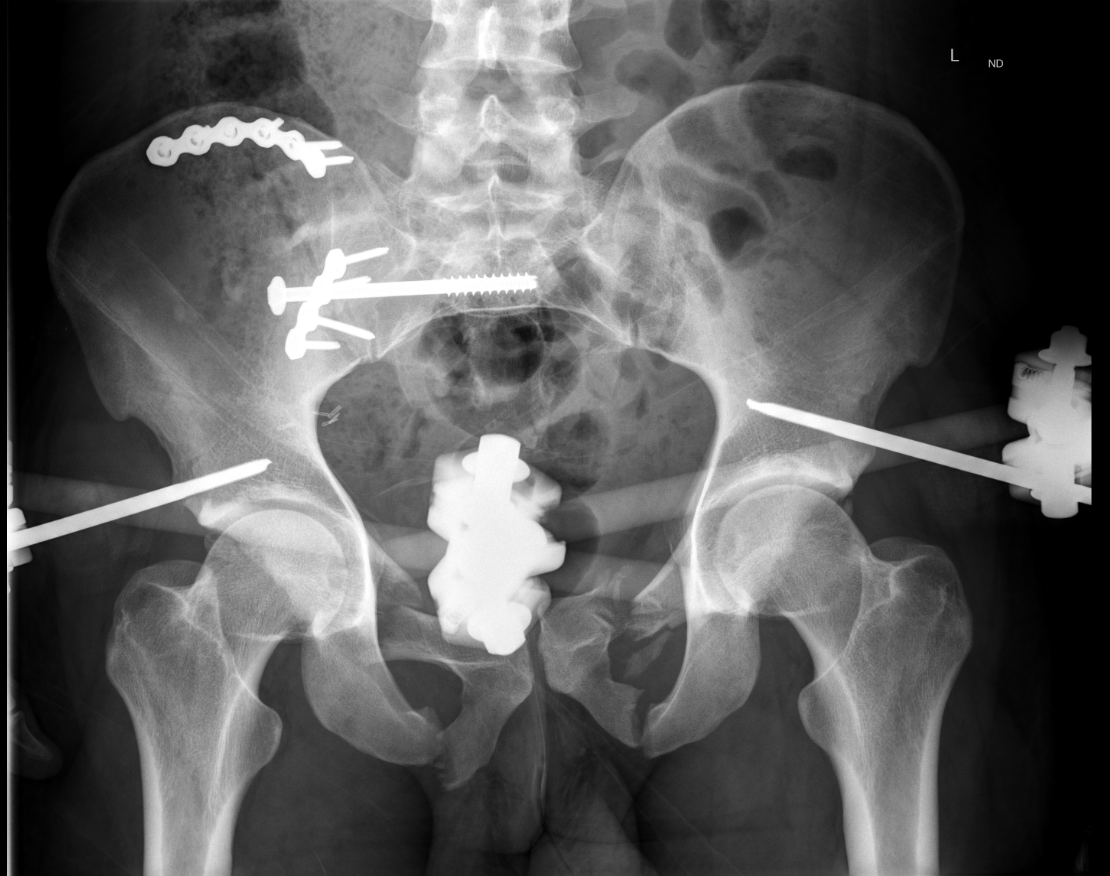

Initial Management

Femoral steinman pin + 20lb weight to reduce vertical displacement

Anterior external fixation to pelvis